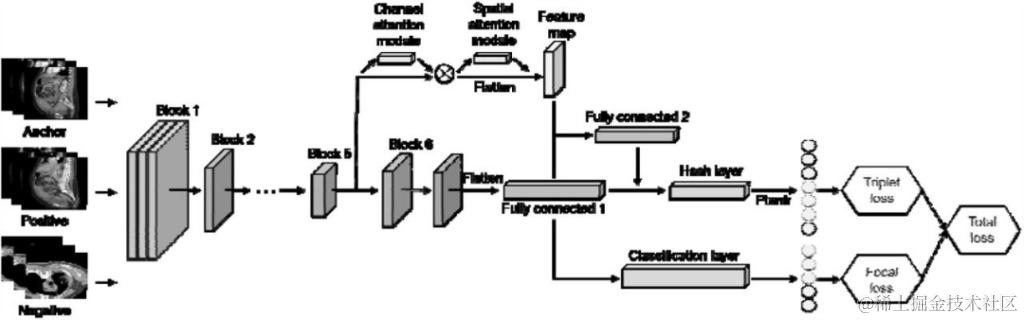

在 OBIA,研究人员以癌症影像数据库 TCIA 的多模态癌症数据为基础,将 EfficientNet 用作特征提取器,使用三元组网络和注意力模块 (attention module) 来训练模型,并将图像压缩为离散哈希值 (图 2)。随后,为加快推理性能并减少推理延迟,训练好的模型被转换为 TensorRT 格式,使用 Faiss 存储哈希码。

研究人员利用汉明距离 (Hamming distance) 计算图像相似度,并返回最相似的图像,结果表明,该模型的平均精度 (MAP) 值超过了 TCIA 数据集上现有高级图像检索模型的性能。

图 2:基于注意力和层融合模块的深度三元组哈希

该模型以 EfficientNet-B6 为主网络,利用 Block5 中的 CBAM 注意模块获取特征映射。在全连接层中采用层融合,利用焦点损失和三元组损失生成哈希码和类嵌入。

注:

● CBAM:convolutional block attention module,卷积块注意力模块

● EfficientNet:Google 于 2019 年提出的新型 CNN 网络,具备极高的参数效率和速度,在图片分类领域表现优异

● Faiss:Facebook 人工智能研究院开发的高性能相似性搜索库,通常用于深度学习